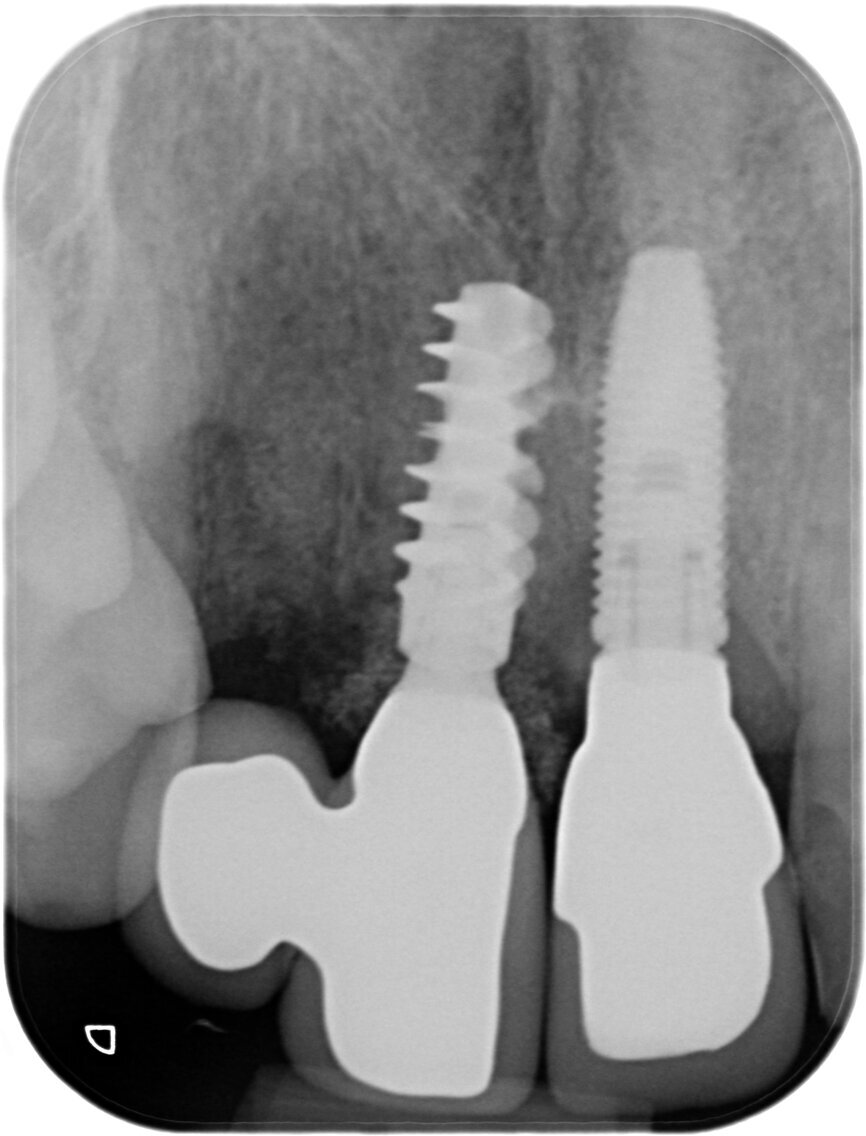

A 52-year-old man, a non-smoker in good general health, was referred after diagnosis of post-traumatic resorption affecting the roots of teeth #11 and #12 (Figs. 1a & 1b). The patient had previously consulted with an endodontist, who stated that both teeth were hopeless and therefore extractions were required. Clinical examination revealed a complete, healthy periodontium around tooth #12 with no sign of infection. At tooth #11, a slight tissue oedema associated with chronic irritation in front of the extensive resorption was observed. The intermaxillary relationship was normal, and the analysis of the smile showed a low smile line (Fig.2). Tooth #21 had been replaced by an implant-supported crown. The previously requested CBCT scan showed that the resorption process was more advanced at tooth #11 (Fig. 3).

We used the previous CBCT scan to evaluate the bone volume in the apical area of teeth #11 and #12, as well as the integrity of the buccal plate at both sites (Fig.4). The examination of the CBCT scan showed that the buccal plate was intact 3 mm below the gingival level and this correlated to the findings of the clinical examination. The future extraction sockets were determined as Class I according to Elian et al.[2]

The bone volume in relation to the axis of the tooth was considered favourable for immediate implant placement, Class I according to Kan et al.[1] However, we knew from the literature that adjacent implants in such a clinical scenario behave poorly because of the small distance between the platform and that in this kind of situation the probability of the inter-implant papillae loss is quite high. We also knew that a staged approach for the extraction of these two incisors would yield better results from a soft-tissue point of view.[3-6]

Tooth #11 was extracted atraumatically without raising a flap or performing an osteotomy (Fig. 4). The extraction socket was meticulously cleaned and rinsed with Betadine. The drilling sequence included 2.2, 2.8, 3.2 and 3.7 mm drills (Fig.5). The implant was placed with a final torque of 80 N cm (Figs. 6 & 7). In its final position, the implant platform lay 4 mm below the ideal gingival margin (at the same level of the adjacent implant platform; Fig.8).